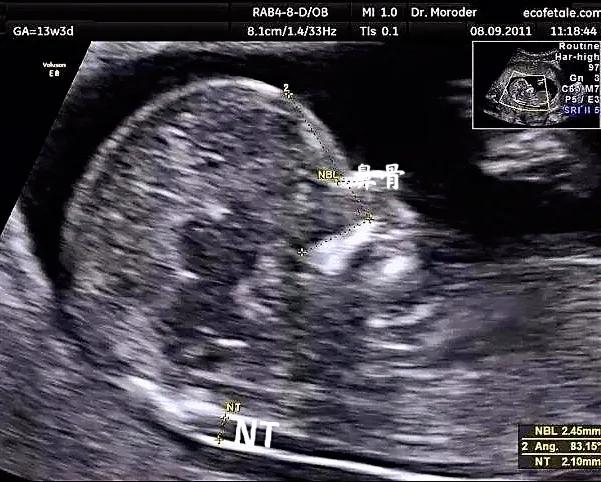

在孕11到孕13周6天之间,检查主要内容:测量NT,也就是胎儿颈后透明带。通过NT数值,结合孕妈的年龄,血清学指标,综合判断胎儿唐氏综合征的风险。除了测量NT,在这次超声时,可以大致进行胎儿一些结构的观察,如有无头颅,有无缺少一侧肢体,有无大的脐膨出等,可以更早期的排除一些严重影响胎儿的结构畸形如:无脑儿等。但是更加详细的结构观察还是要到中孕期的系统筛查,也就是俗称的大排畸。

值得大家期待的是,在我们一妇婴检查超声,您的报告上都会有一张图2所示的宝宝的照片哦。

图2 图中箭头指的就是宝宝的NT